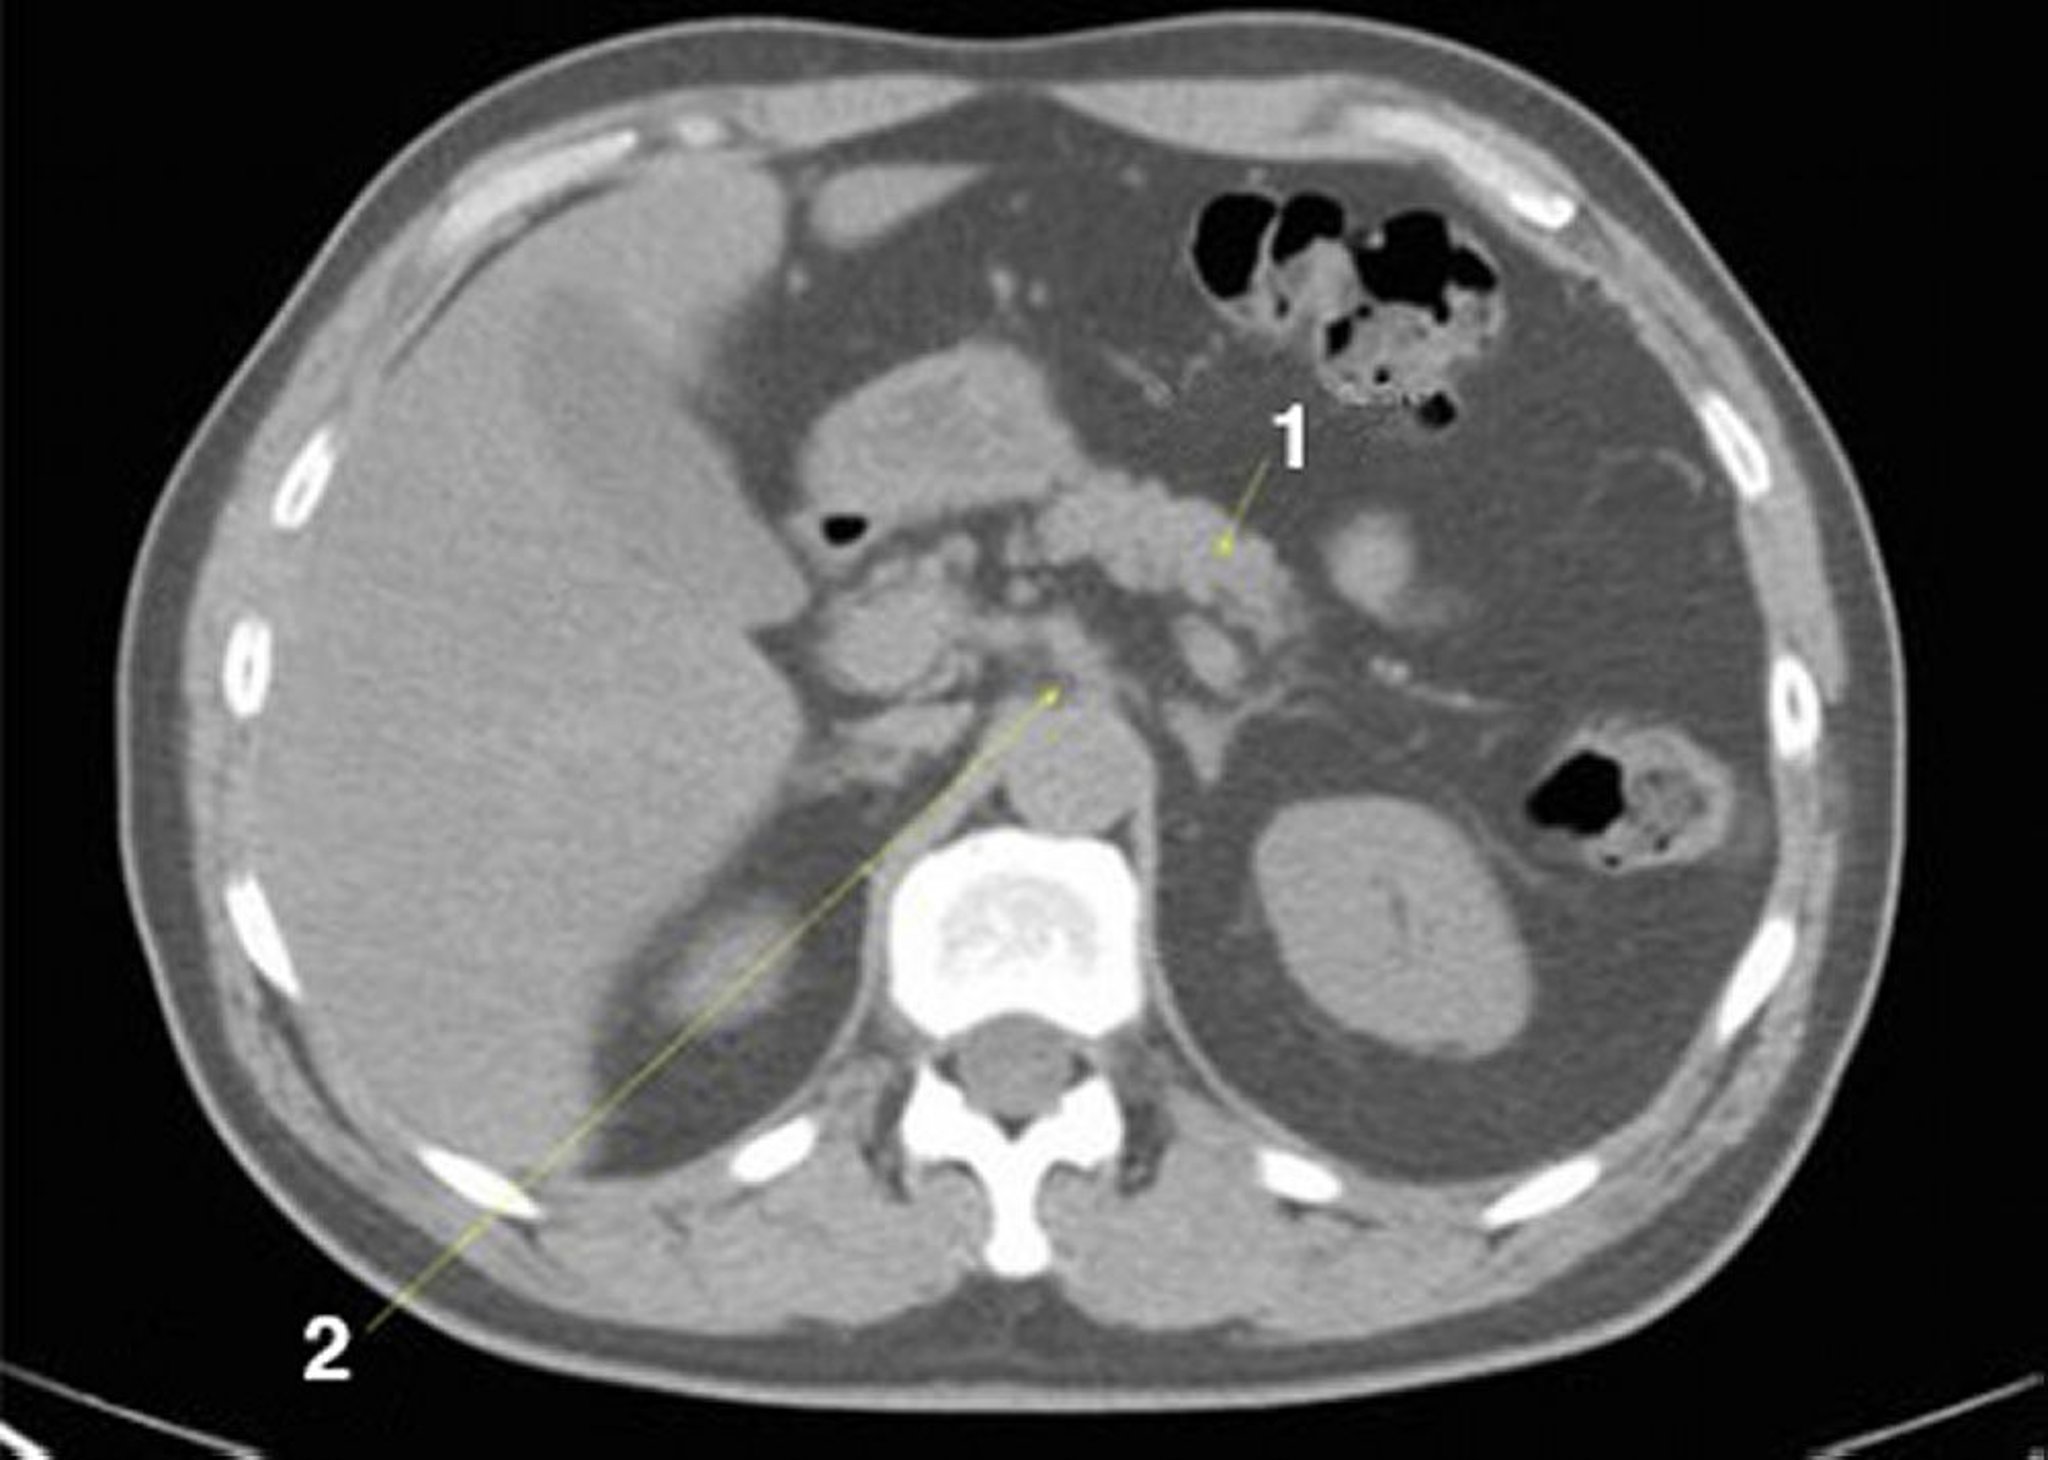

正常解剖を示した腹部および骨盤の単純CT画像(スライド9)

1 = 膵臓;2 = 腹腔動脈。